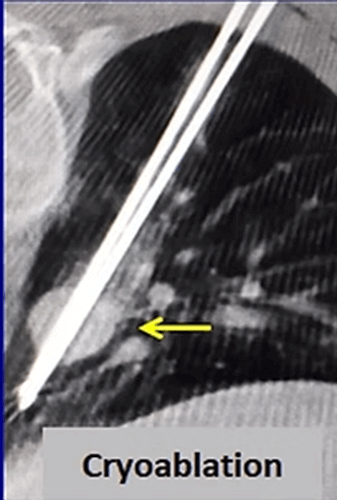

Cryoablation is the newest ablation method in the lung but it is more and more frequently applied for lung cancer. The most important advantages of cryoablation are that it is not painful, can be performed under local anesthesia, can be used in tumors close to the chest wall, the ablation area can be seen as an iceball and larger tumors (> 3cm) can be treated by increasing the number of needles.

In our patient who had a 4x2cm non small cell lung cancer, cryoablation was performed. After the procedure, the 3 and 6 months control CT images show progressive shrinkage of the tumor.

In the same patient, 2 metastases that grew after 2 years were cryoablated using 2 needles. Three months later, the control CT shows that both masses have shrunk and become a residue.